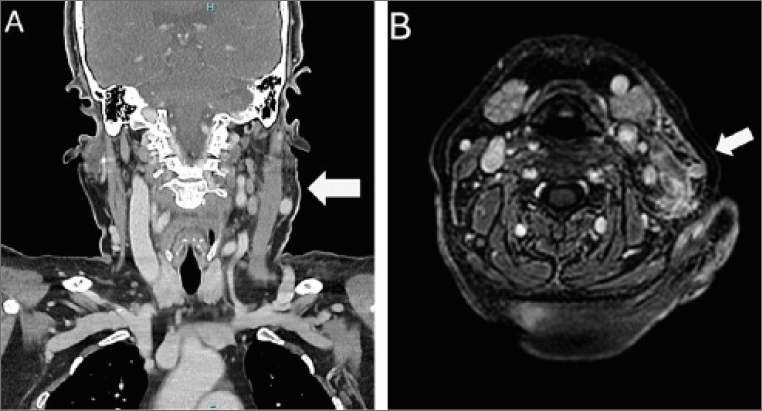

A 78-year-old woman was referred to our neuromuscular disease clinic for evaluation of progressive swelling and pain in the left laterocervical area, which had persisted for several months. Her past medical history included hypothyroidism, hysteroannesectomy for uterine cancer (1989) and atrial fibrillation. Her chronic medications included levothyroxine, edoxaban and esomeprazole. In April 2024, following an episode of respiratory infection, she developed progressive swelling and pain in the left laterocervical region. Initial investigations ordered by her primary care physician included a neck ultrasound, which revealed reactive lymphadenopathy in the left laterocervical region. Otorhinolaryngological evaluation noted increased consistency of the sternocleidomastoid muscle and left submandibular pain without detectable masses. Despite prescribed analgesic and muscle relaxant therapy, the swelling persisted, though pain improved. A contrast-enhanced computed tomography (CT) scan revealed thickening of the left sternocleidomastoid muscle and surrounding soft tissues, with diffuse lymphadenopathy (Fig. 1). In late July 2024, she experienced clinical worsening with increased swelling and fever (38°C), prompting an emergency department visit. She was prescribed cefpodoxime 200 mg twice a day for 6 days and prednisone 25 mg/day for 7 days with subsequent tapering, which provided temporary improvement.

An MRI performed in August 2024 confirmed diffuse inflammation of the left sternocleidomastoid muscle and surrounding soft tissue edema (Fig. 1). During the steroid tapering period, the patient experienced worsening of her local condition, necessitating further specialist referrals.

Figure 1. Imaging findings. (A) Neck CT scan: asymmetric thickening of the left sternocleidomastoid muscle with associated soft tissue swelling (B) Axial MRI (T1-weighted post-gadolinium): extensive inflammatory involvement of the left sternocleidomastoid muscle with contrast enhancement and adjacent soft tissue edema.